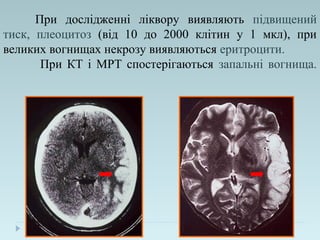

При дослідженні ліквору виявляють підвищений

тиск, плеоцитоз (від 10 до 2000 клітин у 1 мкл), при

великих вогнищах некрозу виявляються еритроцити.

При КТ і МРТ спостерігаються запальні вогнища.